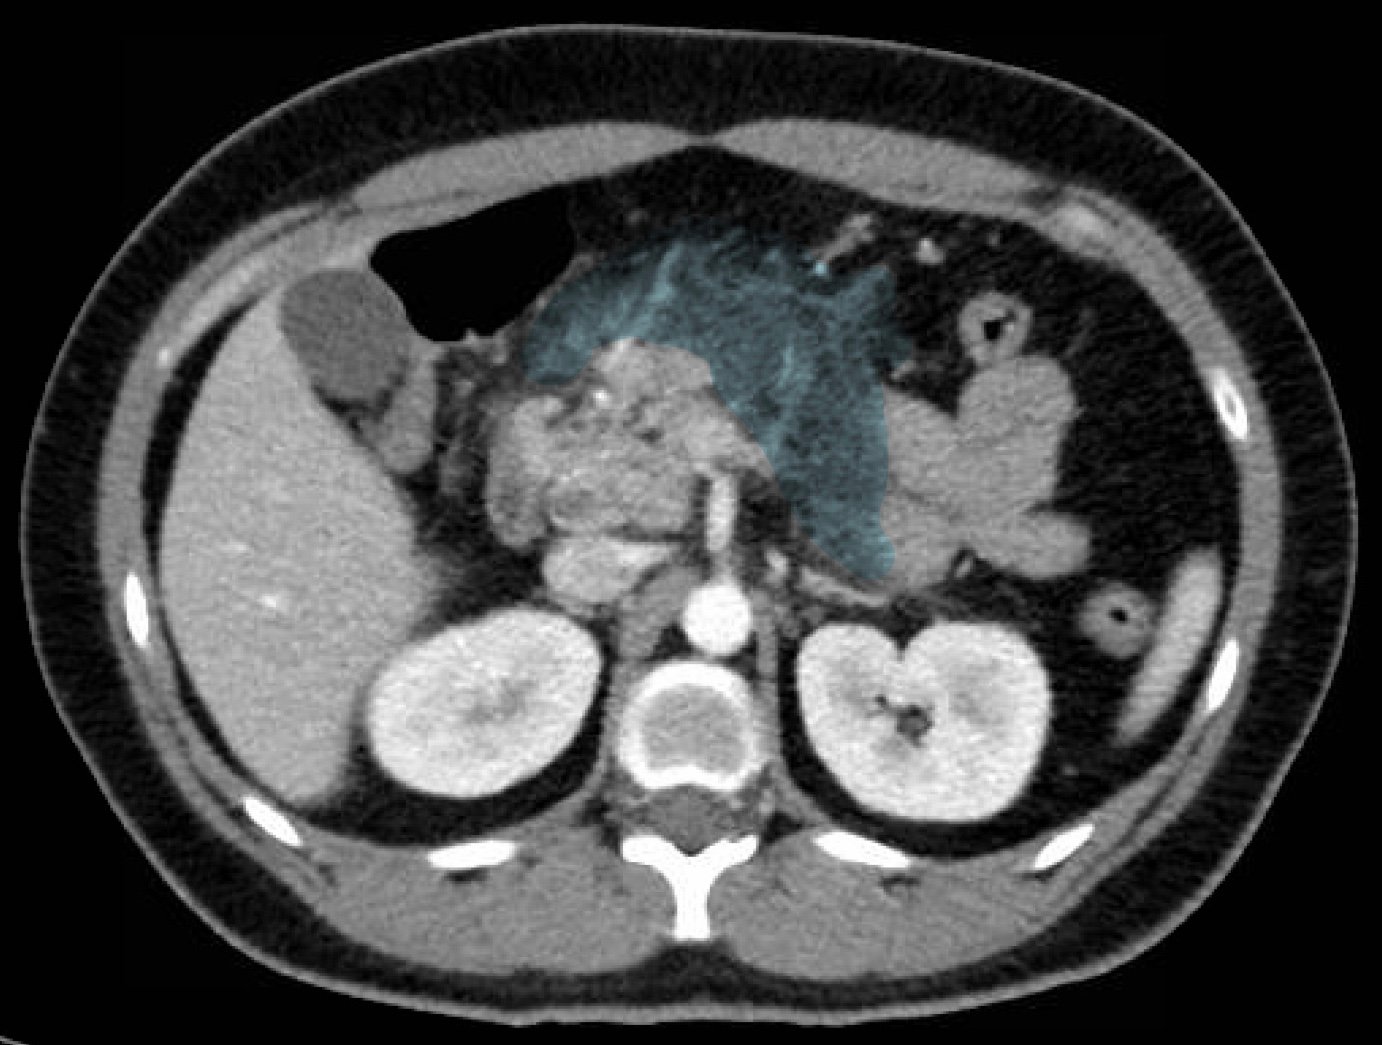

Computed tomography of the abdomen and pelvis with contrast show edema of the pancreas (red outline) and duodenum (yellow arrow) with peripancreatic inflammation, fluid and fat stranding (blue highlight). The distal pancreatic tail was noted to appear normal (green arrow). There was no organized drainable fluid collection, and no parenchymal hypo-enhancement. These findings are consistent with moderate severity acute interstitial pancreatitis.